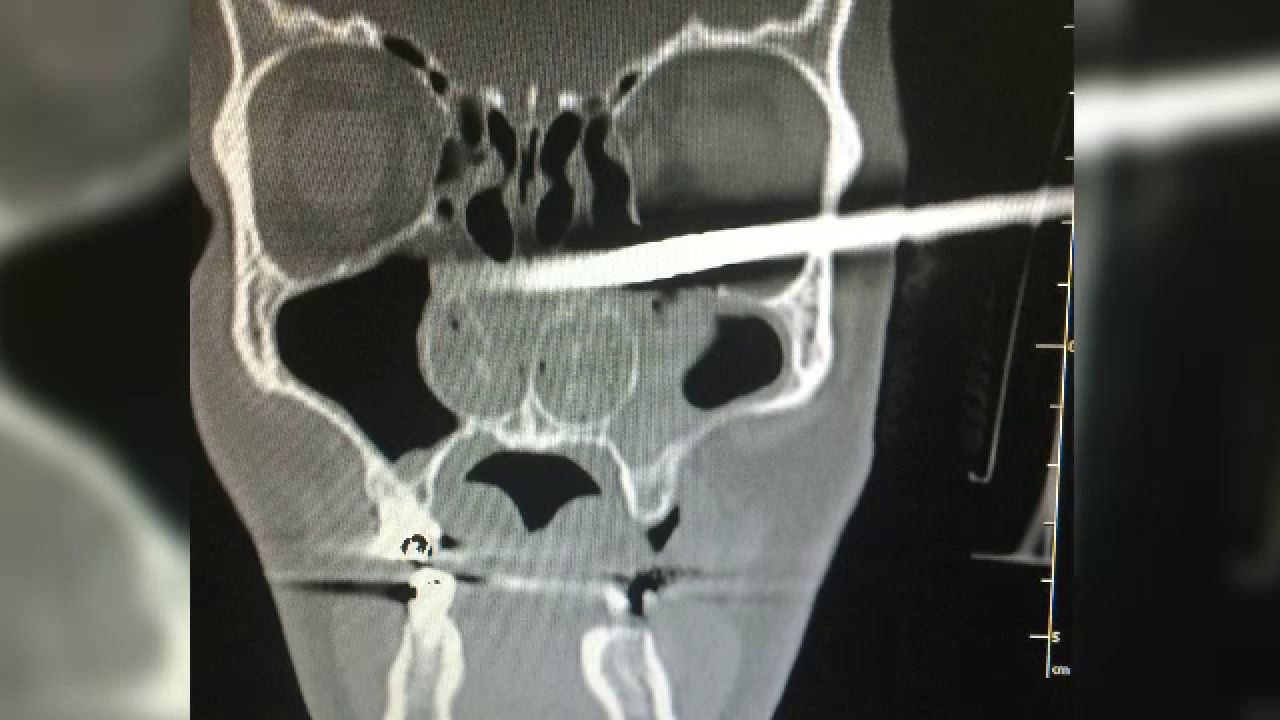

Un barbat din Polonia a ajuns constient la spital cu un cui de 15 centimetri in craniu. Cum a decurs interventia medicala

Un polonez de 45 de ani a scapat teafar dintr-un accident infiorator. Omul a cazut cu capul pe un cui de 15 centimetri care iesea din pamant.

Obiectul din metal i-a patruns in craniu, dar, din fericire, nu i-a atins o zona critica. Era constient cand a ajuns la spital.

Dupa o interventie chirurgicala care a durat doua ore, medici au reusit sa scoata cuiul, respectand traiectoria pe care intrase. Drept urmare, creierul nu a fost afectat, iar pacientul se simte bine.